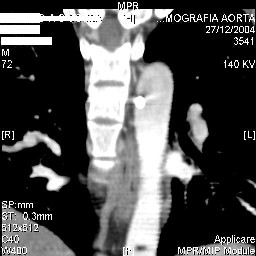

Подошли ангиограммы... Наслаждайтесь...

д-р Архипов

Отправитель: andrew sokoloff 29 Декабрь 2004, 23:58

нонсенс...

травматический обратный дивертикул аорты!

чего планируют: протезирование?

Отправитель: Виктор Княжев 30 Декабрь 2004, 00:01

Мдааа.........

Неприятно, конечно.

Теперь вот шуруп придется менять, потому как если его оставить, то коррозия шурупа неминуема.

Ja esho takogo ni videl! Pokazival ja itot sluchai i neurohirurgam i vascularnim hirurgam, oni vipali v osadok! Da, slozno emu predetsa! Da ksozelenio, Vi kollega okazilis' pravy!!! Luche v takih stuasiah oshebitsa, nizeli okazatsa pravim, no srabotal tut zakon nashei professii - samie hudshie ssenarii, vsegda sbivaiotsa! Ito fact.